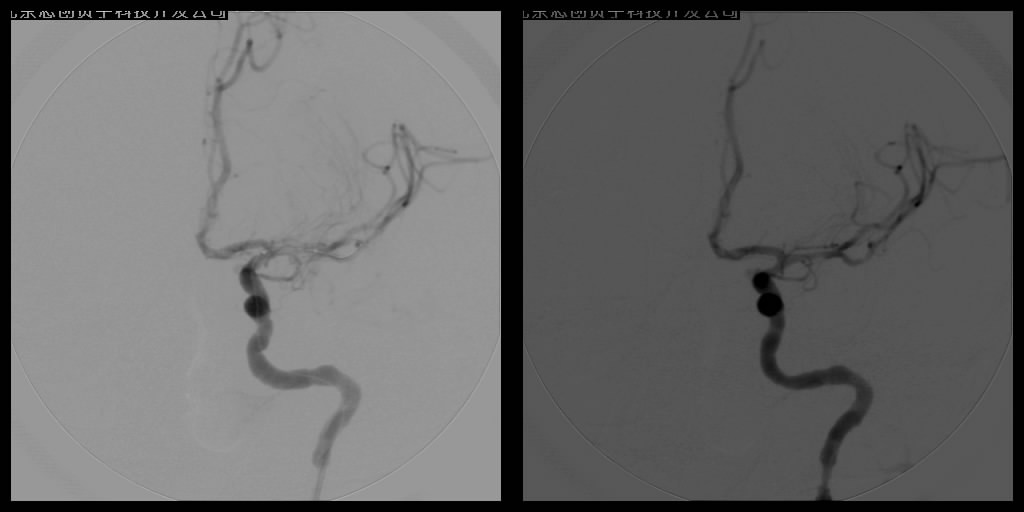

腦梗塞微創(chuàng)介入治療——數(shù)字減影血管造影(DSA)介入治療

血管球囊擴(kuò)張成形術(shù)和血管內(nèi)支架植入成形術(shù)已經(jīng)成為治療腦缺血、腦梗塞十分重要的手段。手術(shù)操作時(shí)在DSA監(jiān)控下,將導(dǎo)引管經(jīng)主動(dòng)脈插到供應(yīng)顱腦的血管——頸動(dòng)脈或椎動(dòng)脈內(nèi),再置放支架,達(dá)到擴(kuò)開狹窄段血管、順性行血流再建的目的,所用支架可分為球囊擴(kuò)張式支架和自膨式支架。DSA系統(tǒng)輔助下的動(dòng)脈血管成形術(shù)不但能清晰明確地了解影像病變,而且在造影過程中就可了解血管內(nèi)血流、血管壁等情況,全面判斷血管結(jié)構(gòu)及功能變化,為確診和治療提供了可靠的依據(jù),已在臨床上取得了良好的療效。

支架植入